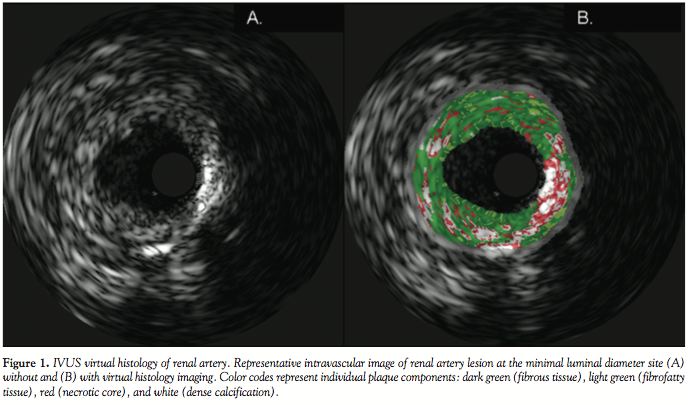

Vessel and lumen dimensions, plaque burden, and VH composition were determined for the entire pullback segment and MLD frame using previously published methods.9 VH plaque composition was analyzed in an automated fashion via Volcano S5 software version 2.2.3.2236. The plaque components were coded by the analysis software as follows: dark green (fibrous tissue), light green (fibrofatty tissue), red (necrotic core), and white (dense calcification) (Figure 1).

IVUS dimensions and VH pullback analysis. An average of 37 ± 15 frames were analyzed for each lesion with a mean VH segment analysis length of 16.2 ± 9 mm. Average plaque volume was 318 ± 178 mm3. The VH component analysis of the segment demonstrated predominantly fibrous tissue (56.3 ± 11.4%), followed by necrotic core (21.8 ± 8.6%), dense calcification (13.2 ± 6.6%) and fibrofatty tissue (8.7 ± 4.0%) (Figure 2).

Analysis of the MLD frames demonstrated a plaque burden of 73.2 ± 16.5%, a minimal lumen diameter of 2.5 ± 0.8 mm, minimal lumen area of 9.1 ± 6.1 mm2, and reference vessel diameter of 5.8 ± 1.2 mm. The VH analysis of the MLD frame demonstrated mostly fibrous tissue (62.1 ± 11.1%) with smaller amounts of necrotic core (15.6 ± 7.3%), fibrofatty (13.9 ± 9.6%), and dense calcification (8.4 ± 6.0%). The comparison between the VH composition of the MLD and the segment analysis revealed a trend toward more fibrous tissue (p = 0.074), less necrotic core (p = 0.095) and less dense calcification (p = 0.075) at the MLD (Figure 2). Furthermore, the MLD frame had significantly more fibrofatty tissue versus the lesion segment (p = 0.041).